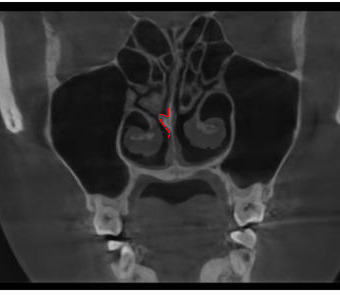

비중격만곡증 자가진단, 생각보다 간단합니다.

비중격이 어느 방향으로 휘어 있는지, 공기 흐름이 좌우로 다르게 느껴지는지만

확인해도 초기 판단에 도움이 됩니다.

전문 장비 없이도 집에서 간단하게 비중격만곡증 여부를 추측해볼 수 있습니다. 다만, 비중격만곡증 자가진단은 어디까지나 의심 단계일 뿐이며, 정확한 진단을

위해서는 이비인후과에서 시행하는 내시경 검사와 CT 촬영이 반드시 필요합니다.

삼성드림이비인후과의 누적된 데이터로 비중격만곡증을 분석합니다.